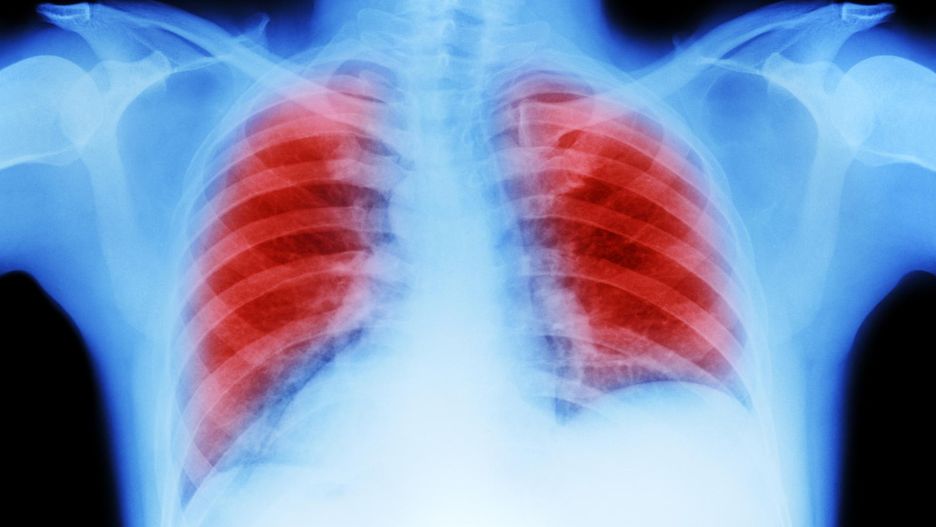

Rak płuca wciąż pozostaje najczęstszą przyczyną zgonów nowotworowych na świecie. Według danych WHO odpowiada za blisko 1,8 miliona zgonów rocznie – to około 18 proc. wszystkich śmierci spowodowanych rakiem. Choć palenie tytoniu nadal jest głównym czynnikiem ryzyka, coraz częściej diagnozuje się tę chorobę u osób, które nigdy nie sięgały po papierosy. U takich pacjentów nowotwór rozwija się inaczej, ma inne podłoże i często lepiej reaguje na nowoczesne terapie celowane.

Rak płuca przez długi czas może nie dawać żadnych wyraźnych symptomów. Wczesne objawy bywają mylone z przeziębieniem, astmą lub zapaleniem oskrzeli, przez co diagnoza często następuje zbyt późno. Do najczęstszych objawów należą:

Światowa Organizacja Zdrowia podkreśla, że szybka reakcja na pierwsze symptomy i wczesne badania diagnostyczne mogą uratować życie.